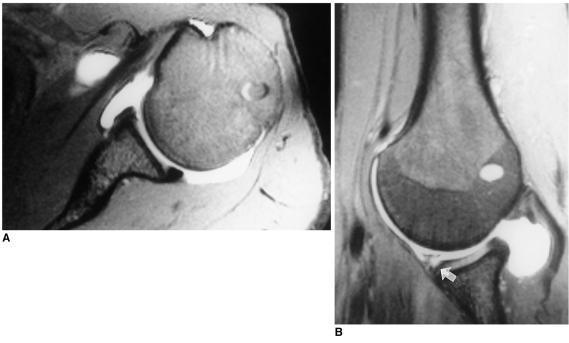

To compare, in terms of their demonstration of tears of the anterior glenoid labrum, oblique axial MR arthrography obtained with the patient's shoulder in the abduction and external rotation (ABER) position, with conventional axial MR arthrography obtained with the patient's arm in the neutral position.

MR arthrography of the shoulder, including additional oblique axial sequences with the patient in the ABER position, was performed in 30 patients with a clinical history of recurrent anterior shoulder dislocation. The degree of anterior glenoid labral tear or defect was evaluated in both the conventional axial and the ABER position by two radiologists. Decisions were reached by consensus, and a three-point scale was used: grade 1=normal; grade 2=probable tear, diagnosed when subtle increased signal intensity in the labrum was apparent; grade 3=definite tear/defect, when a contrast material-filled gap between the labrum and the glenoid rim or deficient labrum was present. The scores for each imaging sequence were averaged and to compare conventional axial and ABER position scans, Student's t test was performed.

In 21 (70%) of 30 patients, the same degree of anterior instability was revealed by both imaging sequences. Eight (27%) had a lower grade in the axial position than in the ABER position, while one (3%) had a higher grade in the axial position. Three whose axial scan was grade 1 showed only equivocal evidence of tearing, but their ABER-position scan, in which a contrast material-filled gap between the labrum and the glenoid rim was present, was grade 3. The average grade was 2.5 (SD=0.73) for axial scans and 2.8 (SD=0.46) for the ABER position. The difference between axial and ABER-position scans was statistically significant (p<0.05).

MR arthrography with the patient's shoulder in the ABER position is more efficient than conventional axial scanning in revealing the degree of tear or defect of the anterior glenoid labrum. When equivocal features are seen at conventional axial MR arthrography, oblique axial imaging in the ABER position is helpful.